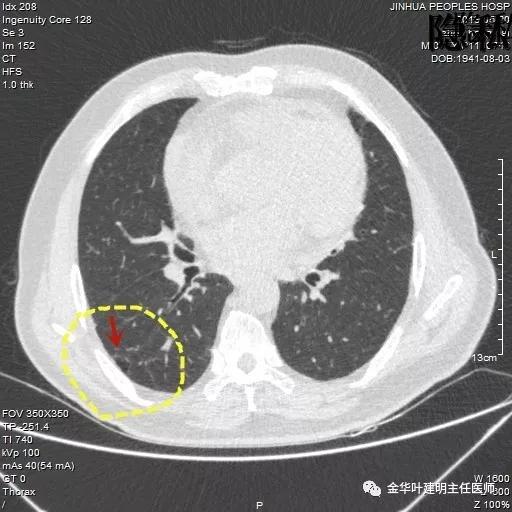

金华的周某,今年已经78岁了,上个月底单位退休人员体检,查出他的右肺有一结节,结果出来后,这个月通知他到胸外科复诊。因为是我的亲戚,便直接找到了我,我从电脑里调出他的CT片,如下所示:

可见其右下叶有一空腔性病灶,壁薄,病灶下方见到实性密度的成份。我们看过目前的片子后,马上想到的是此病灶以前有没有,对比是非常重要的。调出之前片子: